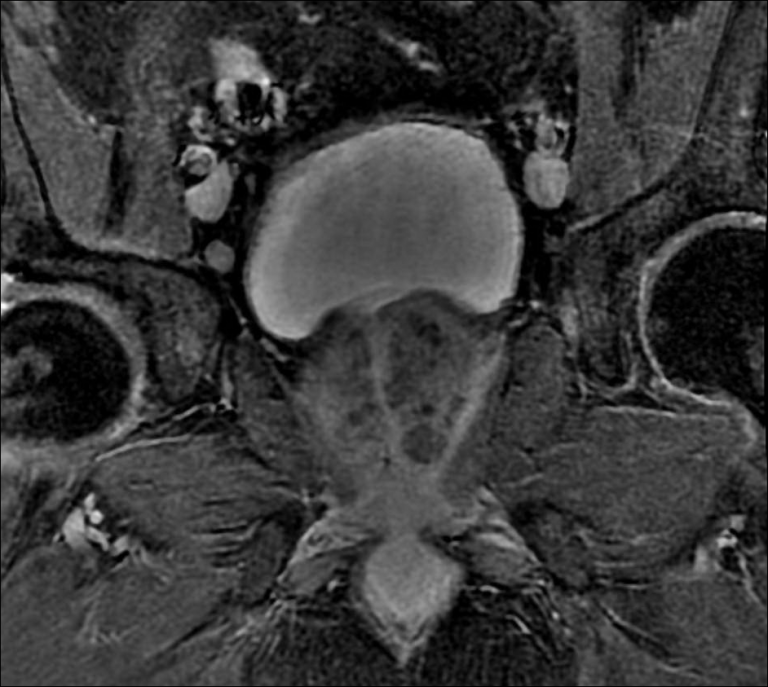

From www.bmj.com

Axial T2 weighted resonance imaging of the male pelvis The BMJ What Is A Mri Pelvis Prostate A prostate mri is an imaging study that gives a clear picture of the prostate. Prostate mris can ensure that you have a. It plays a pivotal role in early. A magnetic resonance imaging (mri) scanner uses strong magnetic fields to create an image (or picture) of the prostate and. This part of the body is called the pelvic area.. What Is A Mri Pelvis Prostate.